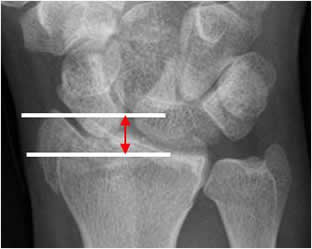

La longitud radial:

Líneas paralelas entre borde final de la apófisis estiloides y el borde inferior de superficie articular. El valor normal es de 11 a 12 mm y se altera en fracturas. (12). (Fig 47 y 48).

Fig 47. Longitud radial normal.

Rx AP. Distancia entre las líneas que pasan por el extremo de la apófisis estiloides del radio y la superficie articular.

Fig 48. Longitud radial. Fractura de radio.

Rx AP. Fractura deprimida de la estiloides radial, con disminución de su longitud.